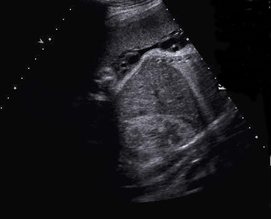

Above. Meconium peritonitis. Case 1. 36 6/7 weeks gestation. Transverse small bowel. Note small bowel dilatation and polyhydramnios.

Above. Meconium peritonitis. Case 1. 36 6/7 weeks gestation. Longitudinal small bowel. Note small bowel dilatation and mesenteric calcifications.

Above. Meconium peritonitis. Case 1. 36 6/7 weeks gestation. Again, note small bowel dilatation and mesenteric calcifications.

Above. Meconium peritonitis. Case 1. 36 6/7 weeks gestation. Note hepatic capsular calcifications and the presence of fetal ascites.